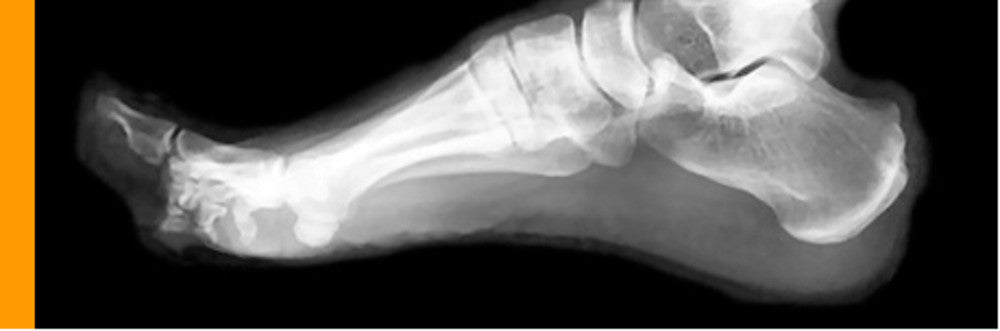

We specialise in the manufacture of precision custom made Foot Orthoses. Orthotics for correction and comfort. Foot Orthoses are devices that fit inside your shoes to help stabilise and correct poor foot posture. Each foot is an engineering masterpiece. The foot is made up of 26 bones, 33 joints and more than 100 muscles, tendons and ligaments. We tend to take this for granted until something goes wrong or we develop pain. This is where we need orthotics.

Bio mechanical problems affecting the feet can increase stresses within the foot structures and the surrounding soft tissues, creating localised pain in the foot and ankle. This can also cause problems in the lower limbs, knees, hips and back. Correction of poor foot bio mechanics with Foot Orthotics can improve and prevent many types of symptoms such as:

Paediatric and adult Pes Plano Valgus feet (flat or collapsed arches) not only cause bio mechanical dysfunction in the feet and ankles but also throughout the body. Foot Orthoses can help correct this condition. The aim of a Foot Orthoses is to correct dysfunctional bio mechanics and therefore:

Foot Orthoses are able to correct the biomechanical collapse of the foot structures and improve mid foot and hind foot alignment. This allows joints to be aligned correctly and promotes efficient transmission of biomechanical forces. We believe in a holistic approach to any biomechanical problem, we understand that the underlying problem may not always be located around the area of the body that develops the symptoms.